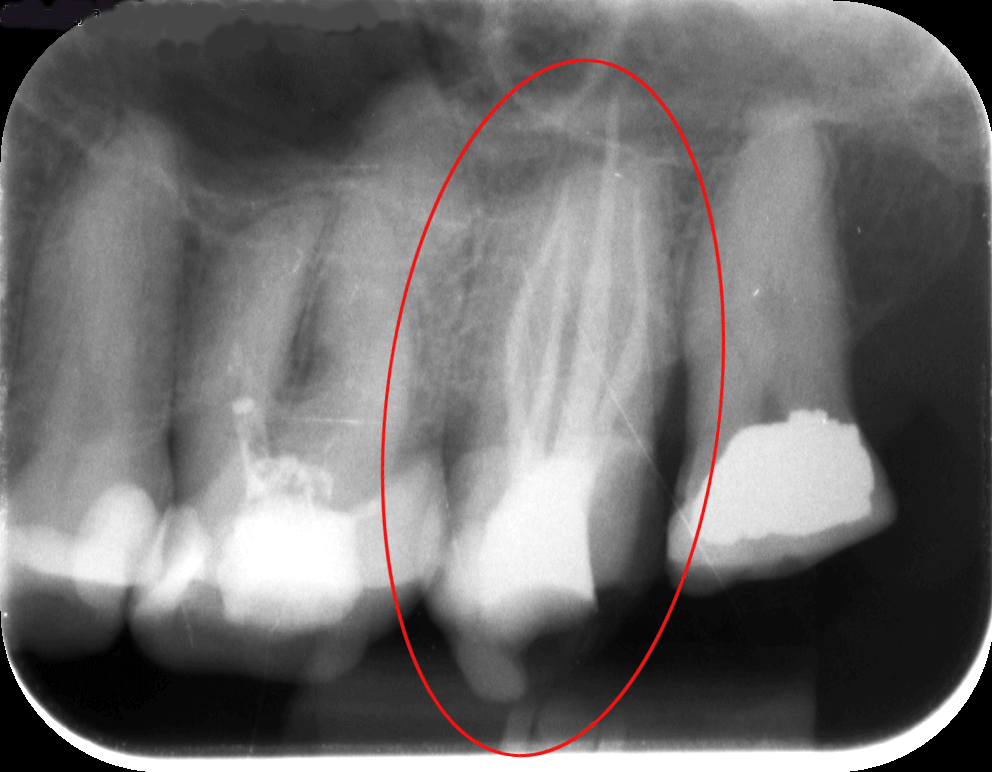

Hölgypáciensünk azért kereste fel rendelőnket, mert a bal felső 7-es foga (az első képen pirossal bekarikázva) állandó sajgását, érzékenységét már tűrhetetlennek érezte. Specialistánk megvizsgálta a röntgenfelvételt, amelyen az érintett fognál 3 foggyökeret lehetett kivenni. Ám fennállt a gyanú, hogy a panaszok okát egy negyedik, „láthatatlan” foggyökérben kell keresni. A kezelőorvos ezért a mikroszkópos kezelés mellett döntött.

mikroszkópos gyökérkezelés előtt